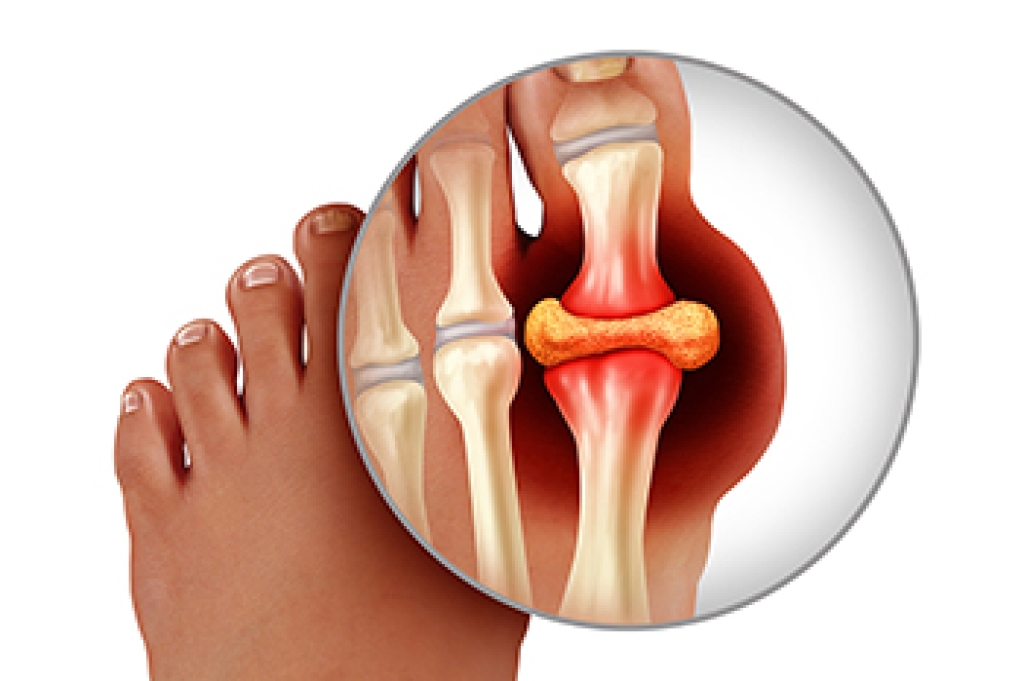

Older individuals usually suffer from heel spurs and pain sometimes intensifies with age. One of the main condition's spurs are related to is plantar fasciitis.

The pain associated with spurs is often because of weight placed on the feet. When someone is walking, their entire weight is concentrated on the feet. Bone spurs then have the tendency to affect other bones and tissues around the foot. As the pain continues, the feet will become tender and sensitive over time.